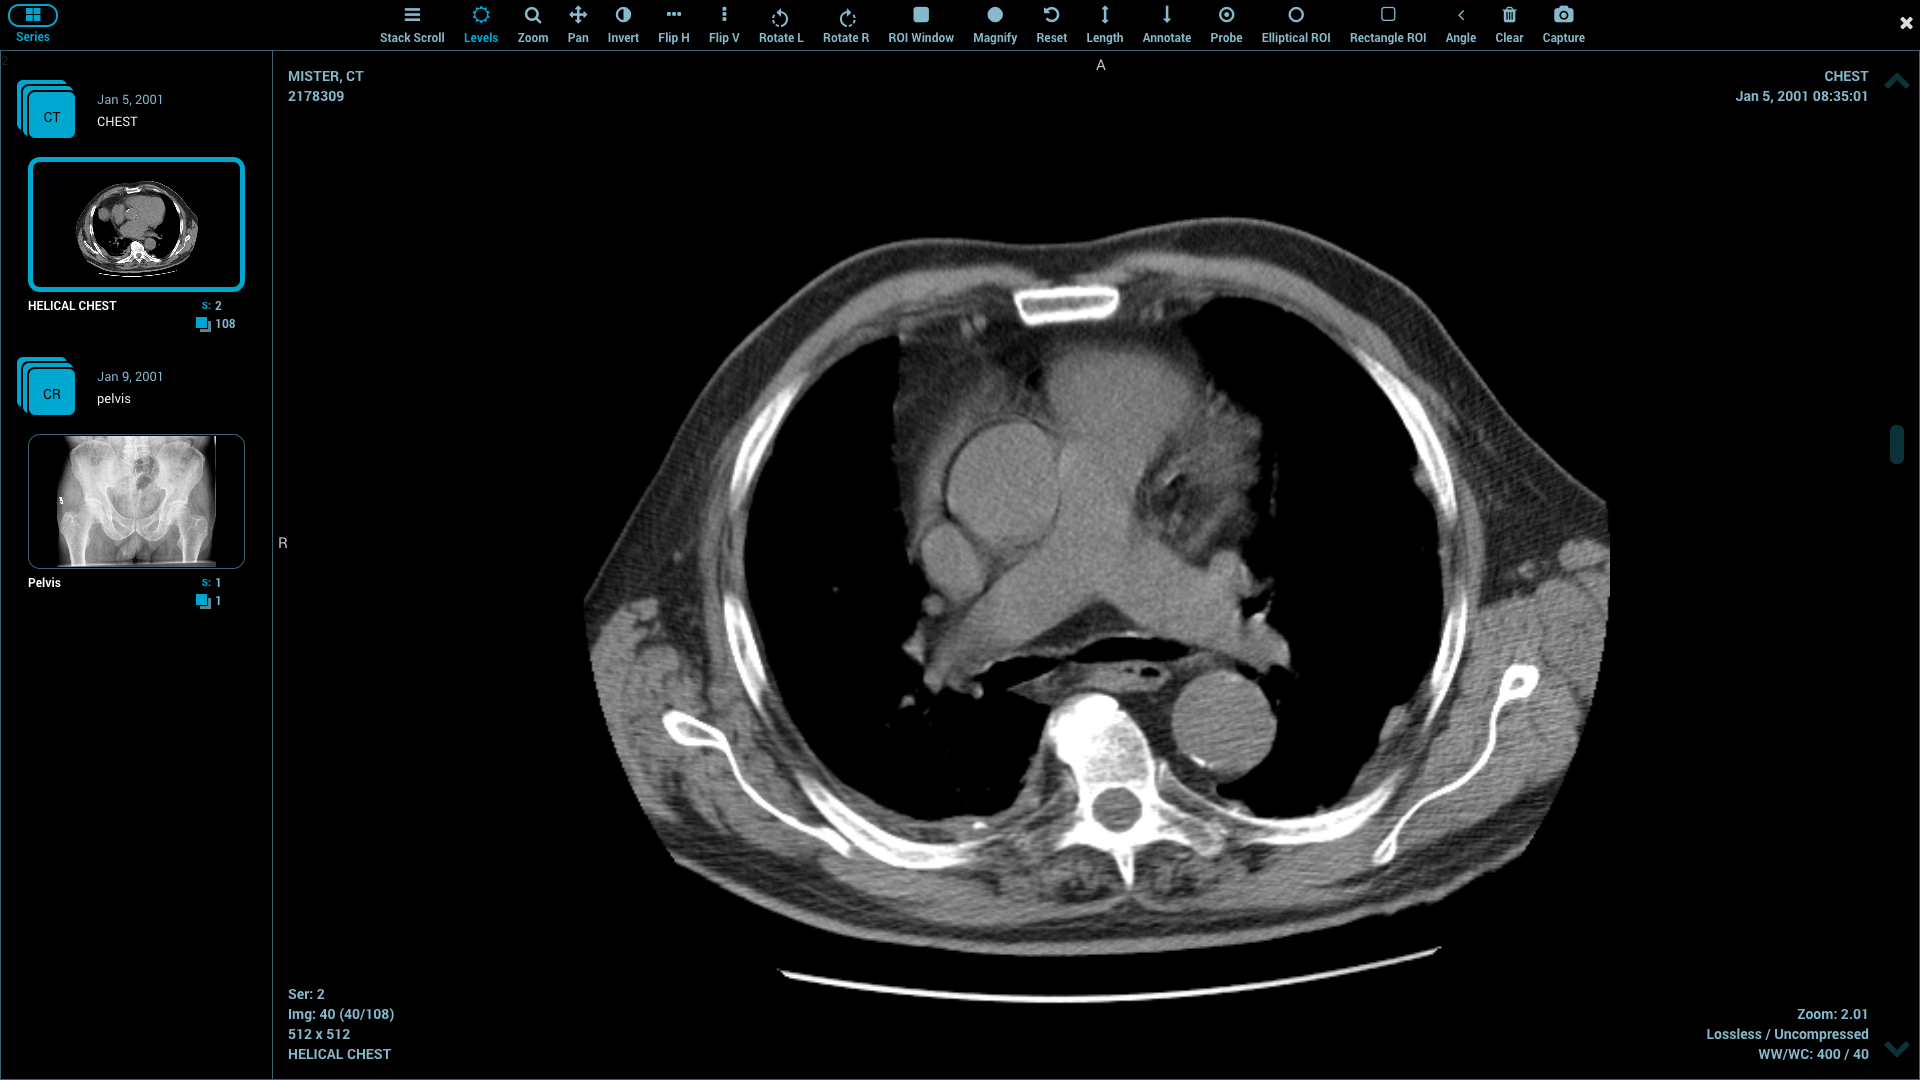

A DICOM library should be able to sustain critical functions of imaging. Metadata and pixel data can be properly read using file parsing. Tag management will guarantee patient and study data safety. Multiple transfer syntaxes are supported, which enhances compatibility.

The decoding of images should not compromise the quality of diagnostics. The characteristics of communication facilitate storage and retrieval of data between DICOM networking protocols. Crash protection is provided by error handling through the handling of malformed files.

Medical imaging data are voluminous and complicated. The images have to be processed by the libraries promptly with no loss in performance. Quick parsing enhances responsiveness on the applications. Memory management eliminates system instability during massive loading of studies.

The progressive image rendering is provided with streaming capabilities. Multi-threading enhances work on the current hardware. Multi-frame images can be accurately handled to aid superior modalities. Optimization of performance cuts down wait time in clinicians.